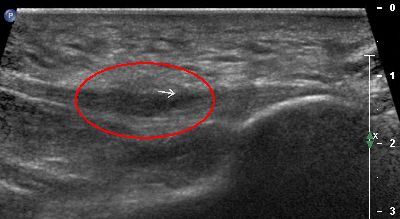

Flogosi plantare (img. 02) flogosi plantare 02